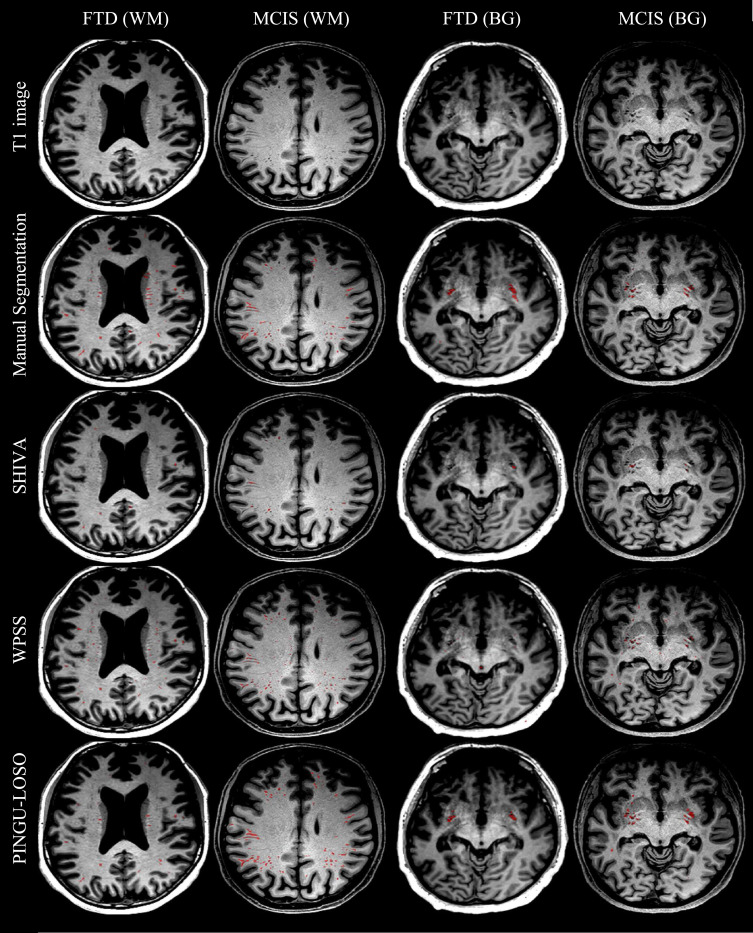

图3.三种深度学习算法分割结果在T1图像上的叠加,并与"高质量"数据集MCIS和"低质量"数据集FTD的手动分割进行比较。显示切片是根据白质(WM)和基底神经节(BG)中PVS体积最大的切片自动选择的。